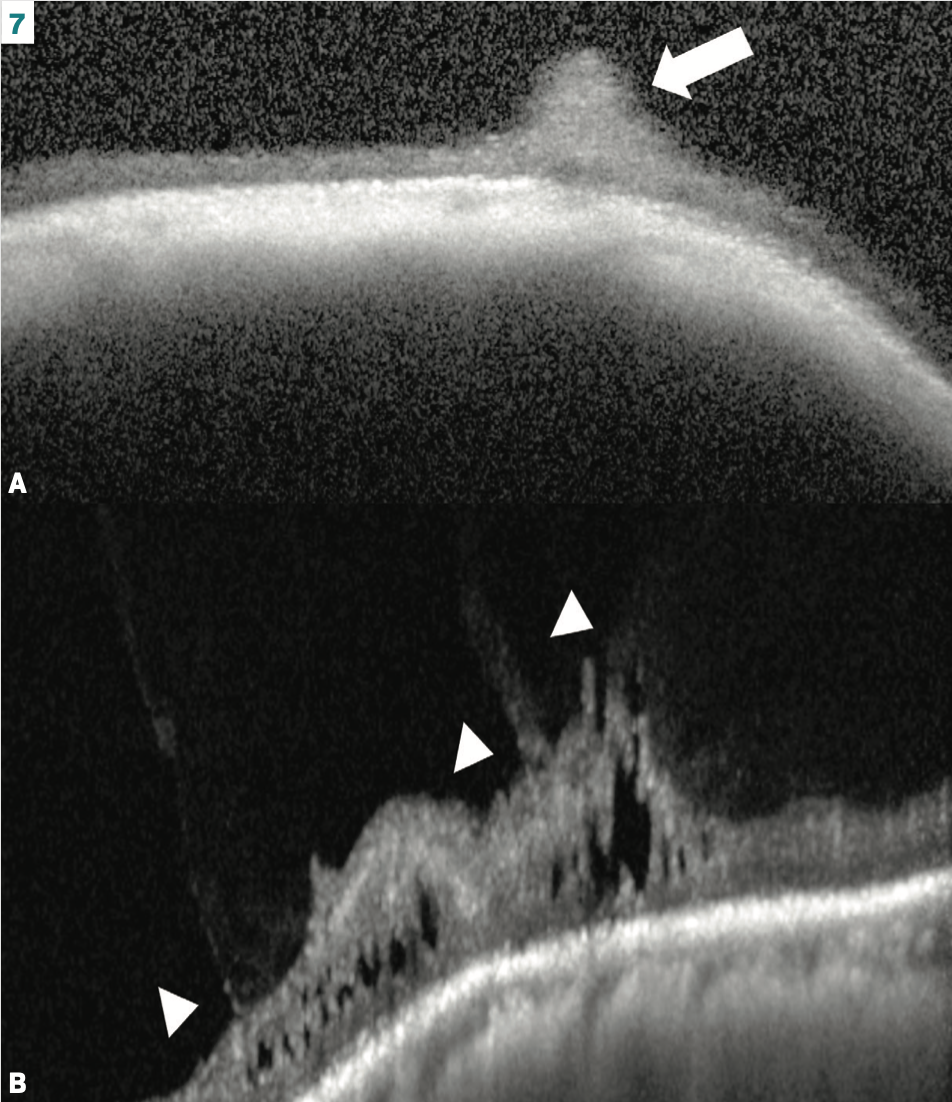

Not all retinal tufts are created equal

Although noncystic retinal tufts typically do not lead to retinal detachment, cystic retinal tufts can. Retinal tears around cystic retinal tufts are estimated to cause 10% of rhegmatogenous retinal detachments.5 Making this distinction clinically is difficult and is much easier with P-OCT (Figure 7).